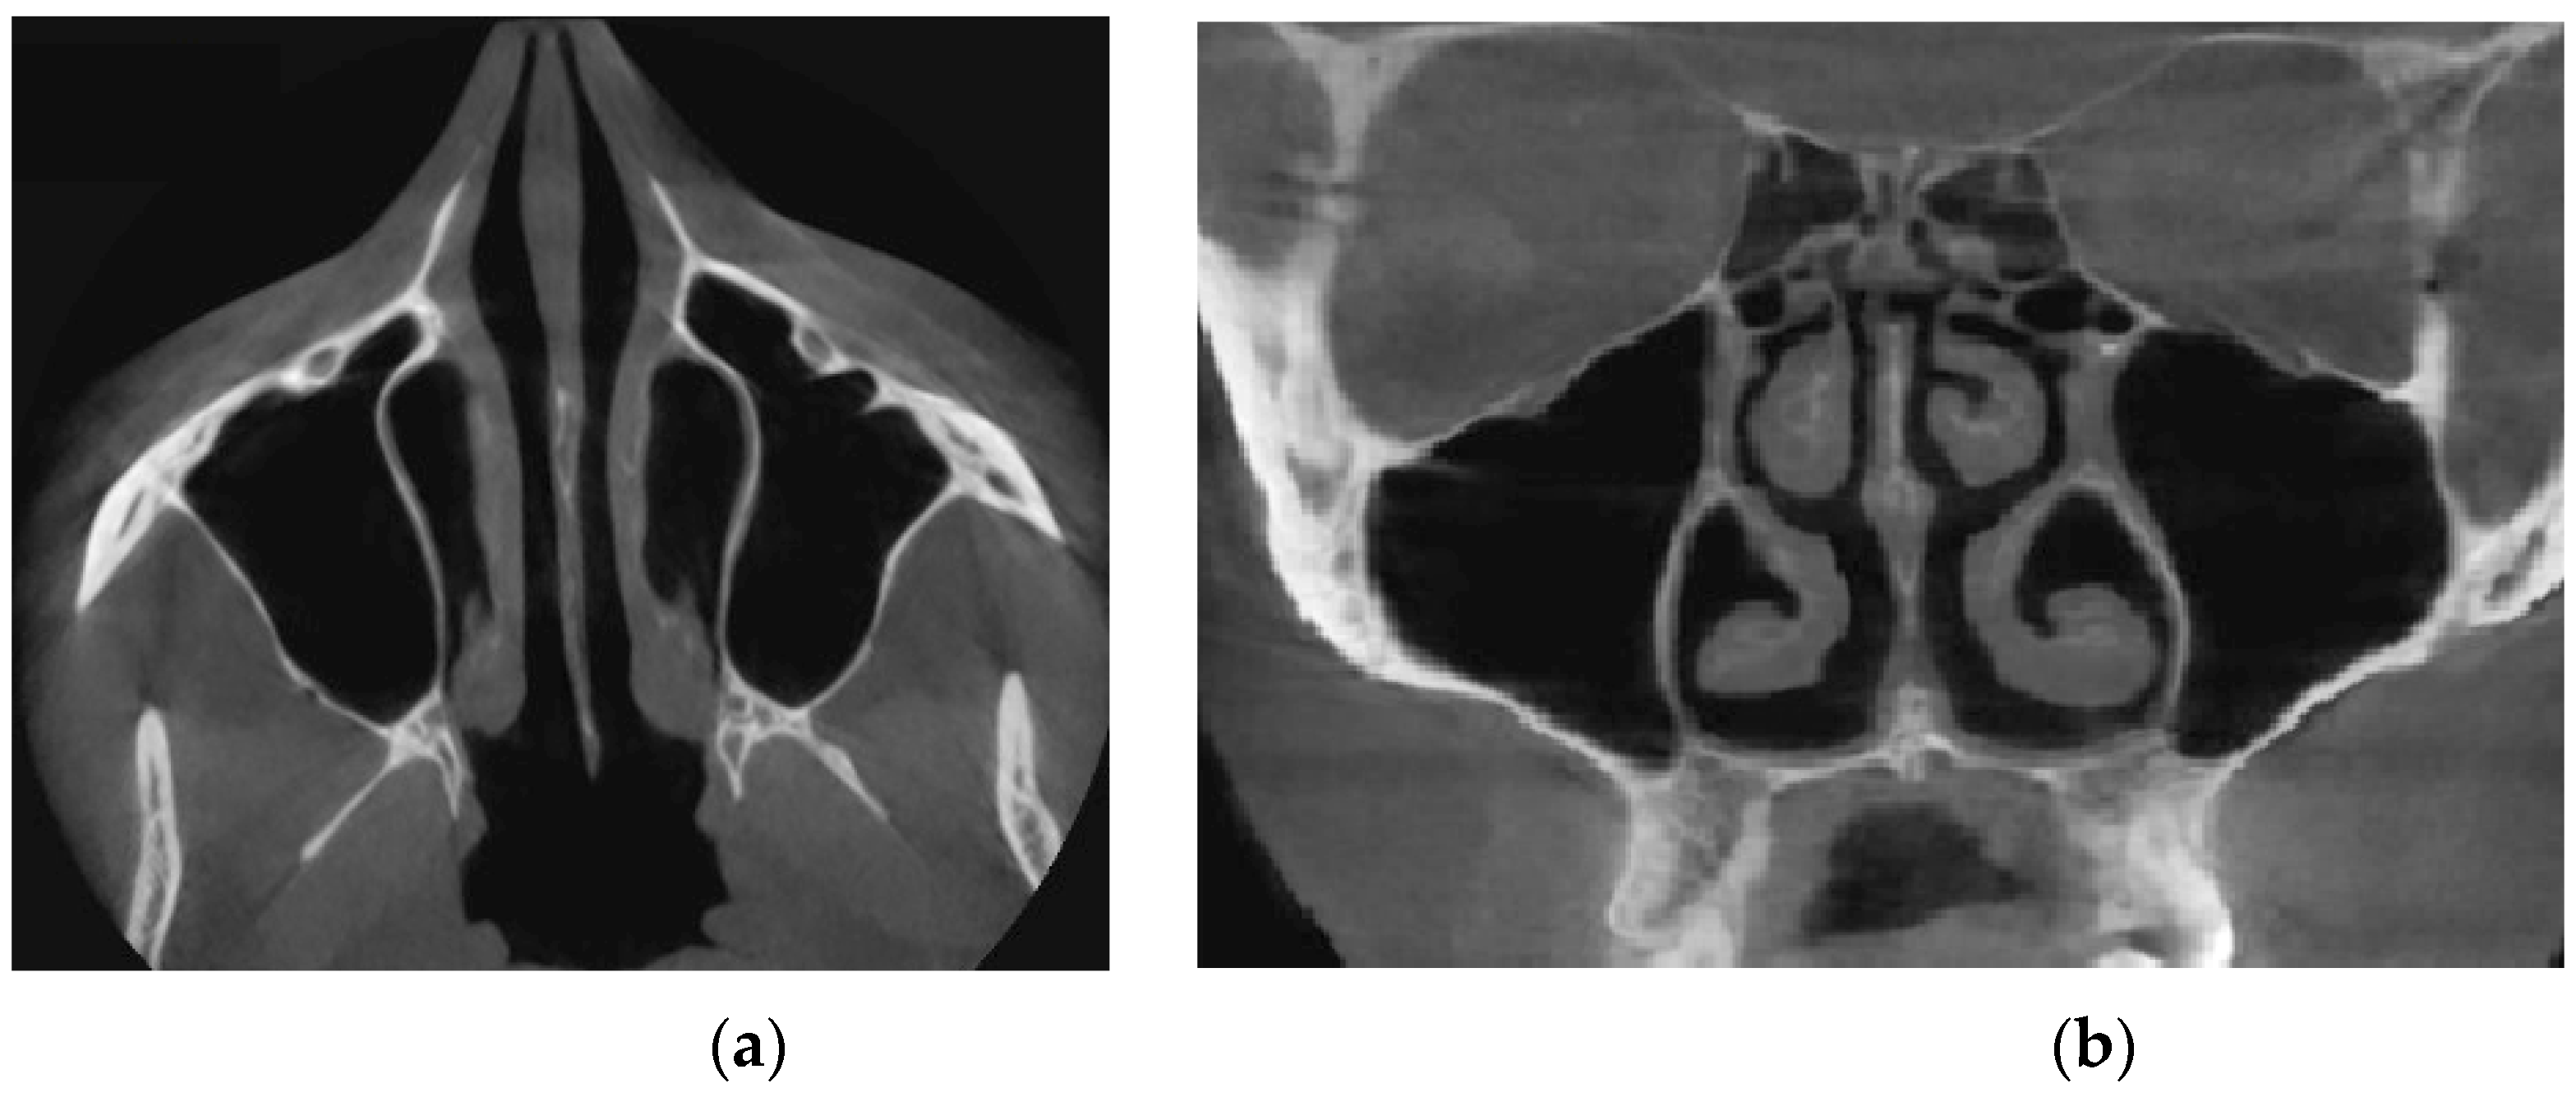

Figure 14 provides a visualization of the local curvature of the nasal septum to the left in the posterior part of the nasal cavity, which is displayed on the axial—see Figure 14, and the frontal—Figure 14b tomographic sections.

Figure 15 shows the thickening of the nasal mucosa in chronic rhinosinusitis, which leads to narrowing of the airways (see Figure 15a,b).